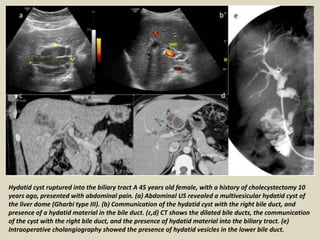

Hydatid cyst ruptured into the biliary tract A 45 years old female, with a history of cholecystectomy 10

years ago, presented with abdominal pain. (a) Abdominal US revealed a multivesicular hydatid cyst of

the liver dome (Gharbi type III). (b) Communication of the hydatid cyst with the right bile duct, and

presence of a hydatid material in the bile duct. (c,d) CT shows the dilated bile ducts, the communication

of the cyst with the right bile duct, and the presence of hydatid material into the biliary tract. (e)

Intraoperative cholangiography showed the presence of hydatid vesicles in the lower bile duct.

Hydatid cyst rupturedinto the biliary tract A 45 years old female, with a history of cholecystectomy 10 years ago, presented with abdominal pain. (a) Abdominal US revealed a multivesicular hydatid cyst of the liver dome (Gharbi type III). (b) Communication of the hydatid cyst with the right bile duct, and presence of a hydatid material in the bile duct. (c,d) CT shows the dilated bile ducts, the communication of the cyst with the right bile duct, and the presence of hydatid material into the biliary tract. (e) Intraoperative cholangiography showed the presence of hydatid vesicles in the lower bile duct.